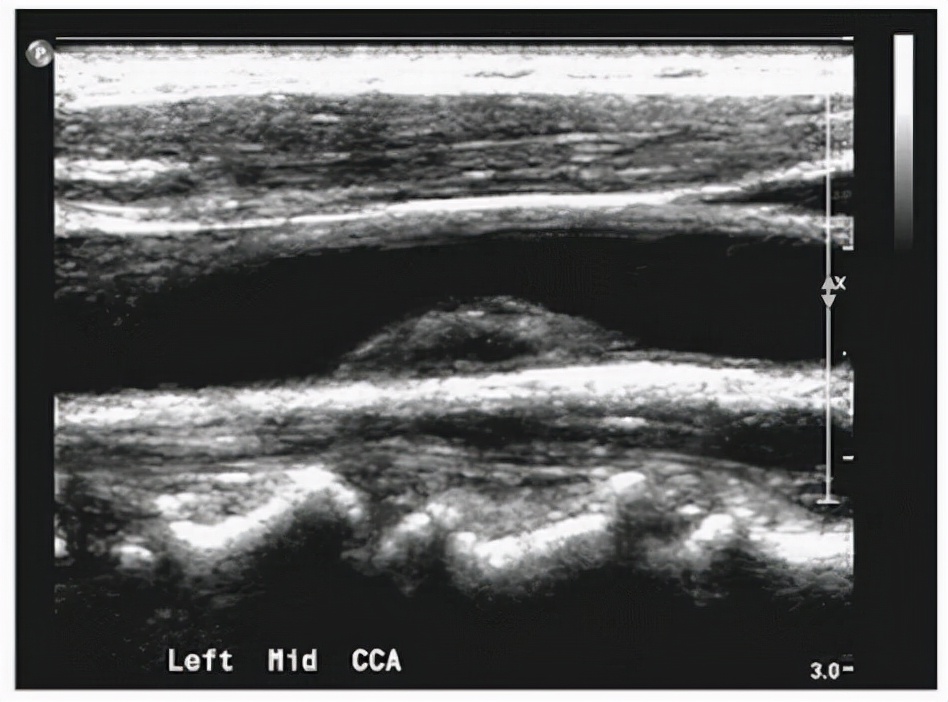

一、高密度脂蛋白胆固醇 。具体看看大爷报告单里升高的是哪一项 , 其实是高密度脂蛋白胆固醇 , 这种胆固醇虽然也是血脂 , 不过这是好血脂 。

我们所说的血脂一般可以分为两类 , 一类是甘油三酯 , 一类是胆固醇 。

而胆固醇也可以分为两种 , 包括高密度脂蛋白胆固醇以及低密度脂蛋白胆固醇 。

但是注意最后一项 , 高密度脂蛋白胆固醇可没那么简单 , 他并不是血管的最大敌人 , 而是血管的亲密战友 , 可以帮助对抗血管老化 。

有很多研究都表明 , 如果是高密度脂蛋白胆固醇增高 , 那么心脏方面发生疾病的可能性会显著下降 。

甚至有研究表明 , 如果单纯提高高密度脂蛋白胆固醇的水平 , 那么会延缓 , 甚至预防冠心病的发生 。

更进一步探讨研究人员发现高密度脂蛋白胆固醇的水平 , 如果每增加1mg/dl , 那么心血管疾病的发生风险就会降低2%~3% 。